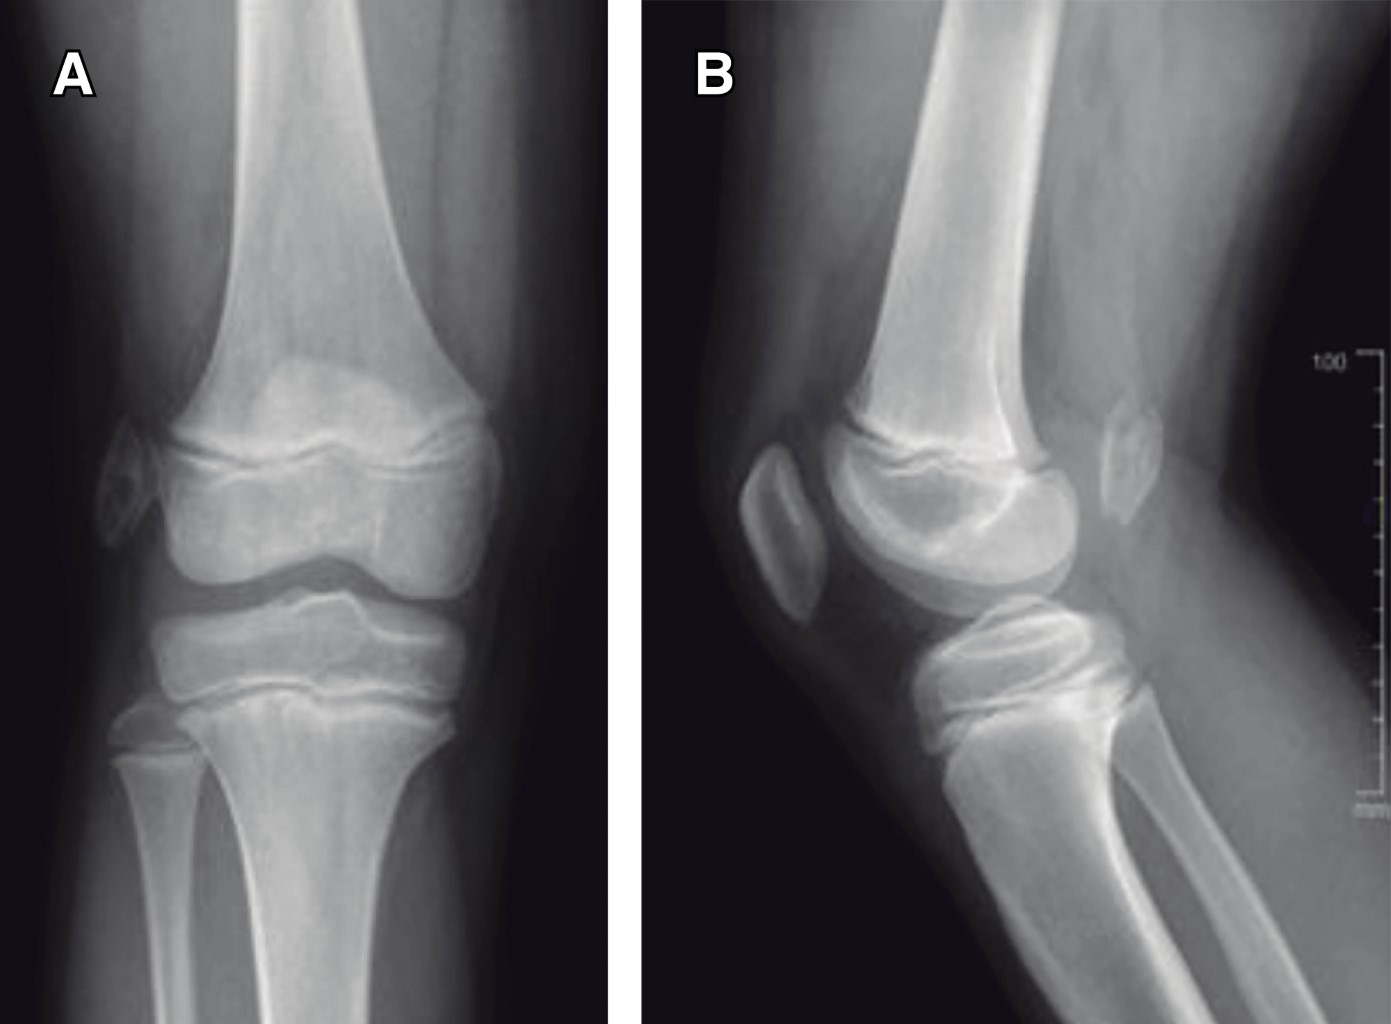

Introduction: myositis ossificans (MO) is described as a non-neoplasic heterotopic bone formation at soft tissues and muscle. It is a rare entity in children, but it must be included within the differential diagnosis of a malignant tumor or an infection. Material and methods: the objective of this retrospective study is to describe three clinical cases of circumscribed myositis ossificans; the first one is a 10-year-old girl with a post-traumatic cervical injury, the second one is an 11-year-old boy with an atraumatic-type distal thigh injury, and the third one is an 8-year-old boy with a post-traumatic right thigh tumor. Results: the diagnosis was made on the basis of the clinical presentation, radiologic imaging and histopathological findings. The results obtained by conservative treatment were good in all cases, with resolution of pain and progressive reduction in size of lesions, without registering complications during follow-up. Conclusion: myositis ossificans is a rare entity, whose diagnosis is usually complex and may require a multidisciplinary team, and whose prognosis is nevertheless favorable.

Figure 3